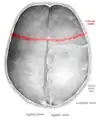

![]() منظر علوي للجمجمة. الدرز الإكليلي مبين باللون الأحمر. منظر علوي للجمجمة. الدرز الإكليلي مبين باللون الأحمر. | |